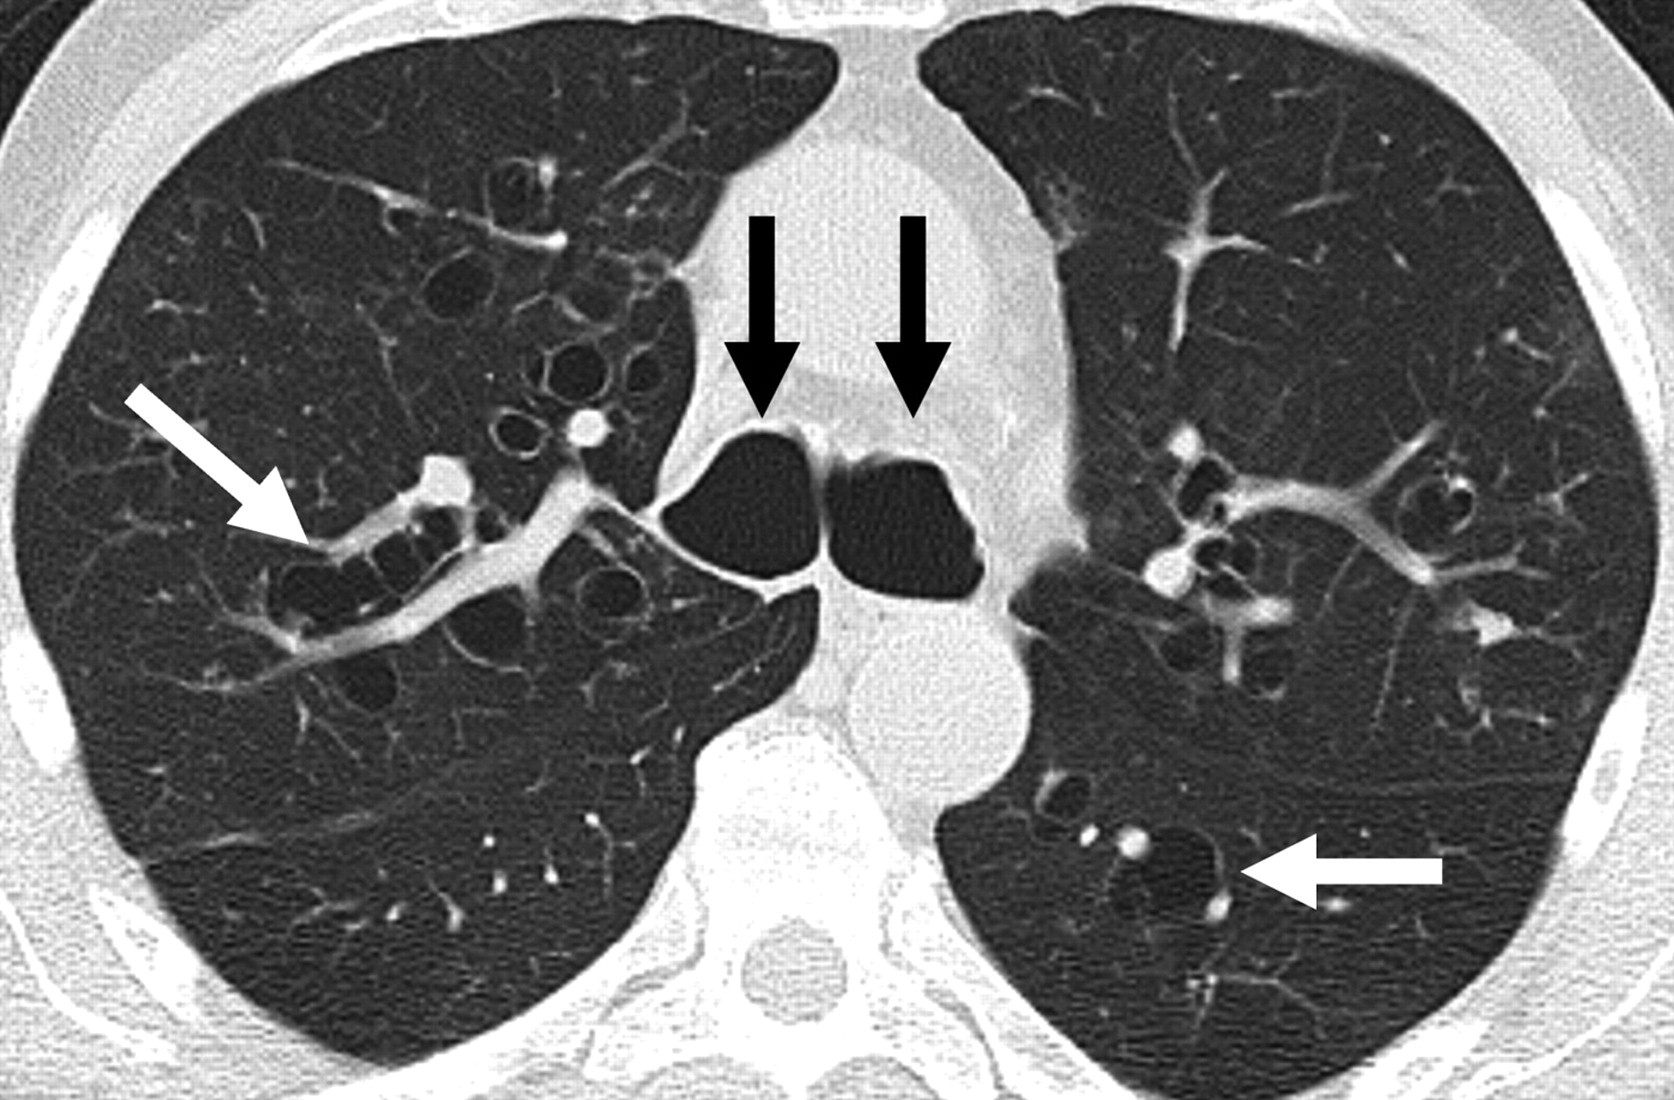

HRCT showing bronchiectasis with signet ring sign and dilated airways

Fig. 1. HRCT of the chest showing bronchiectasis — dilated thick-walled bronchi with the signet ring sign (broncho-arterial ratio >1.5) and tram-track appearance. Cylindrical pattern in this case. Via Wikimedia Commons. CC BY-SA 3.0.

Tram-track signParallel thickened bronchial walls, uniform calibre, no taperingCylindrical bronchiectasis

Signet ring signBroncho-arterial ratio >1.5 — dilated bronchus beside normal arteryDiagnostic of bronchiectasis

Cluster of grapesDilated cystic bronchi to pleural surface with air-fluid levelsSevere cystic/saccular disease

Reid classification: Three morphological types in increasing severity — cylindrical (tubular), varicose, and cystic/saccular.